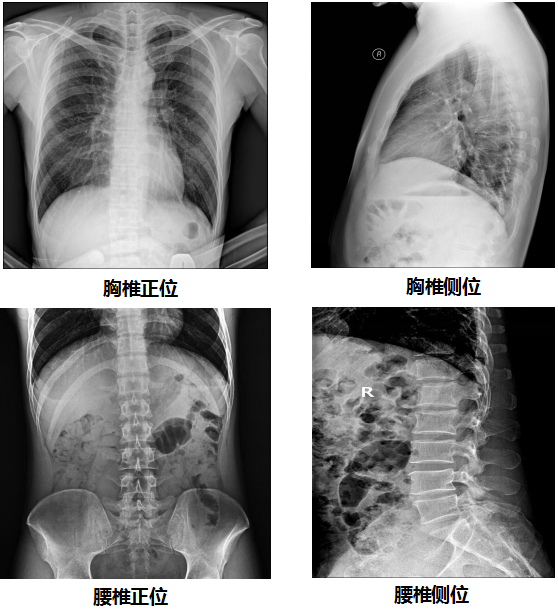

【U直臂DR部分临床效果图】